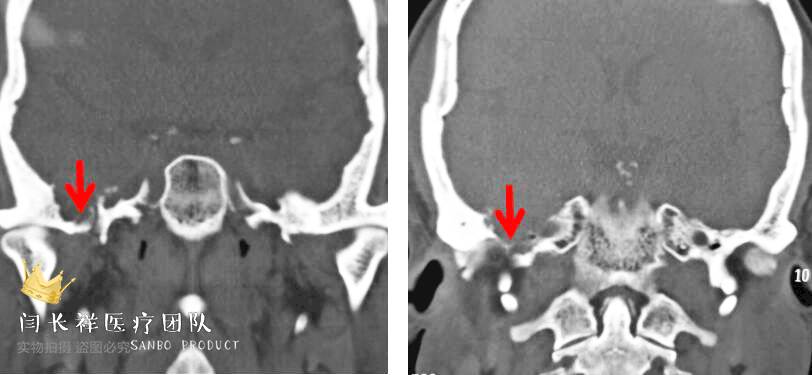

术前冠位CT骨窗像示右侧中颅窝底骨质被肿瘤侵蚀破坏。

中颅窝-颞下窝占位